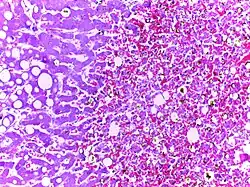

![]() |

Fatty change in liver | Hepatic parenchymal cell cytoplasm containing clear vacuoles containing fat of varying sizes, displacing the nucleus towards the periphery. | Category: Lipid steatosis | steatosis |